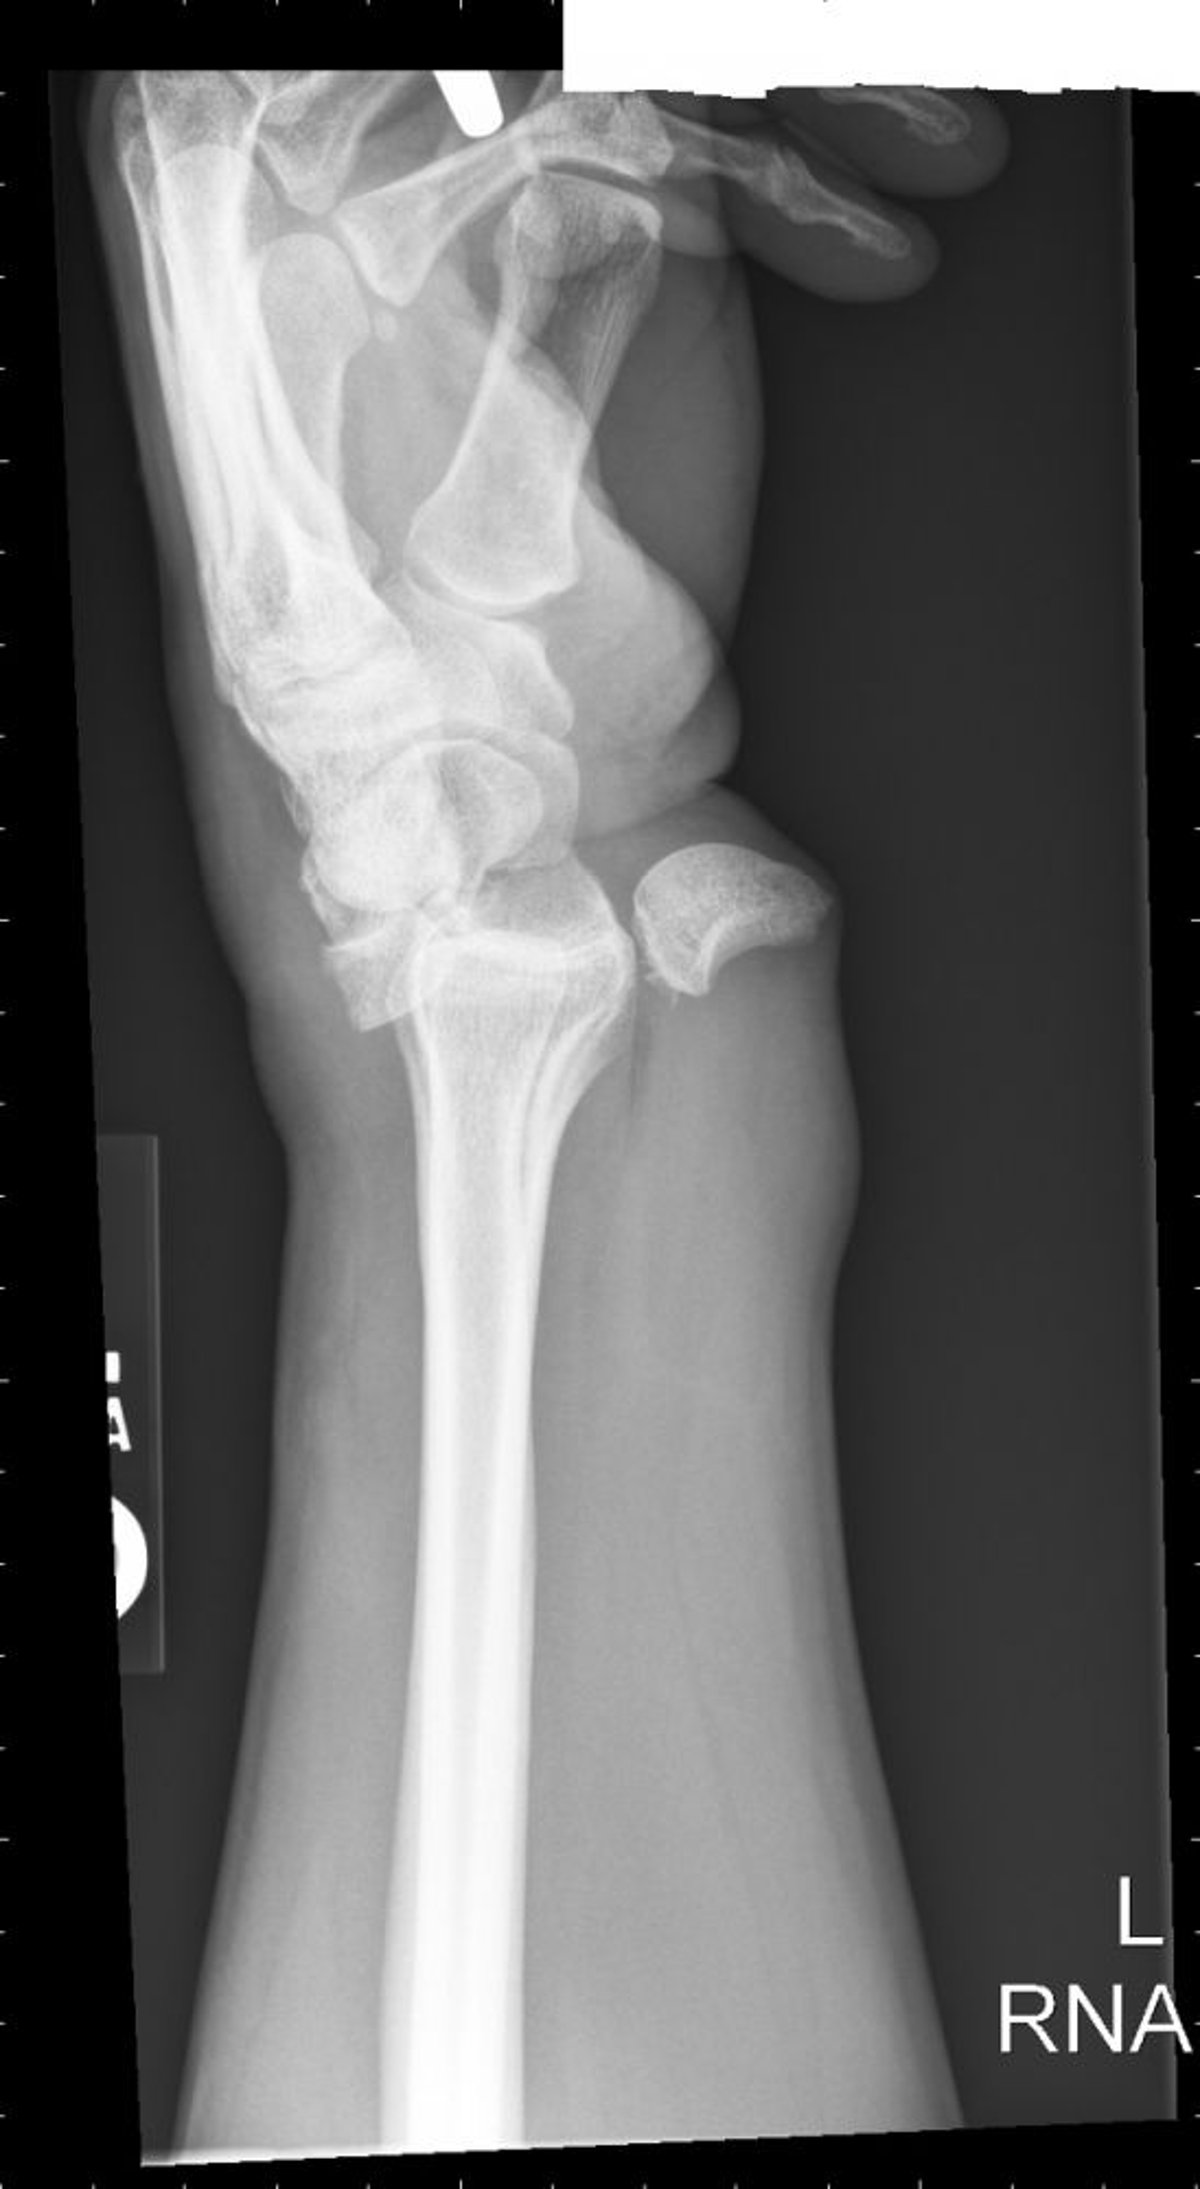

Dislokation des Lunatum

Eine lunäre Dislokation, führt zu einer "verschütteten Teetassen"-Konfiguration.

Image courtesy of Danielle Campagne, MD.